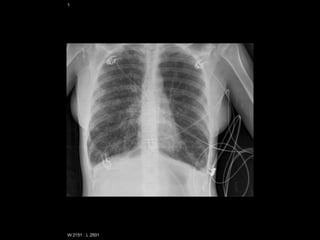

Impresión general

• Presencia de vías centrales, marcapasos, válvulas

protésicas, desfibriladores, lañas sutura, etc.

• Artefactos: trenzas, medallas, botones o decoración

de la ropa, cremalleras, piercings…